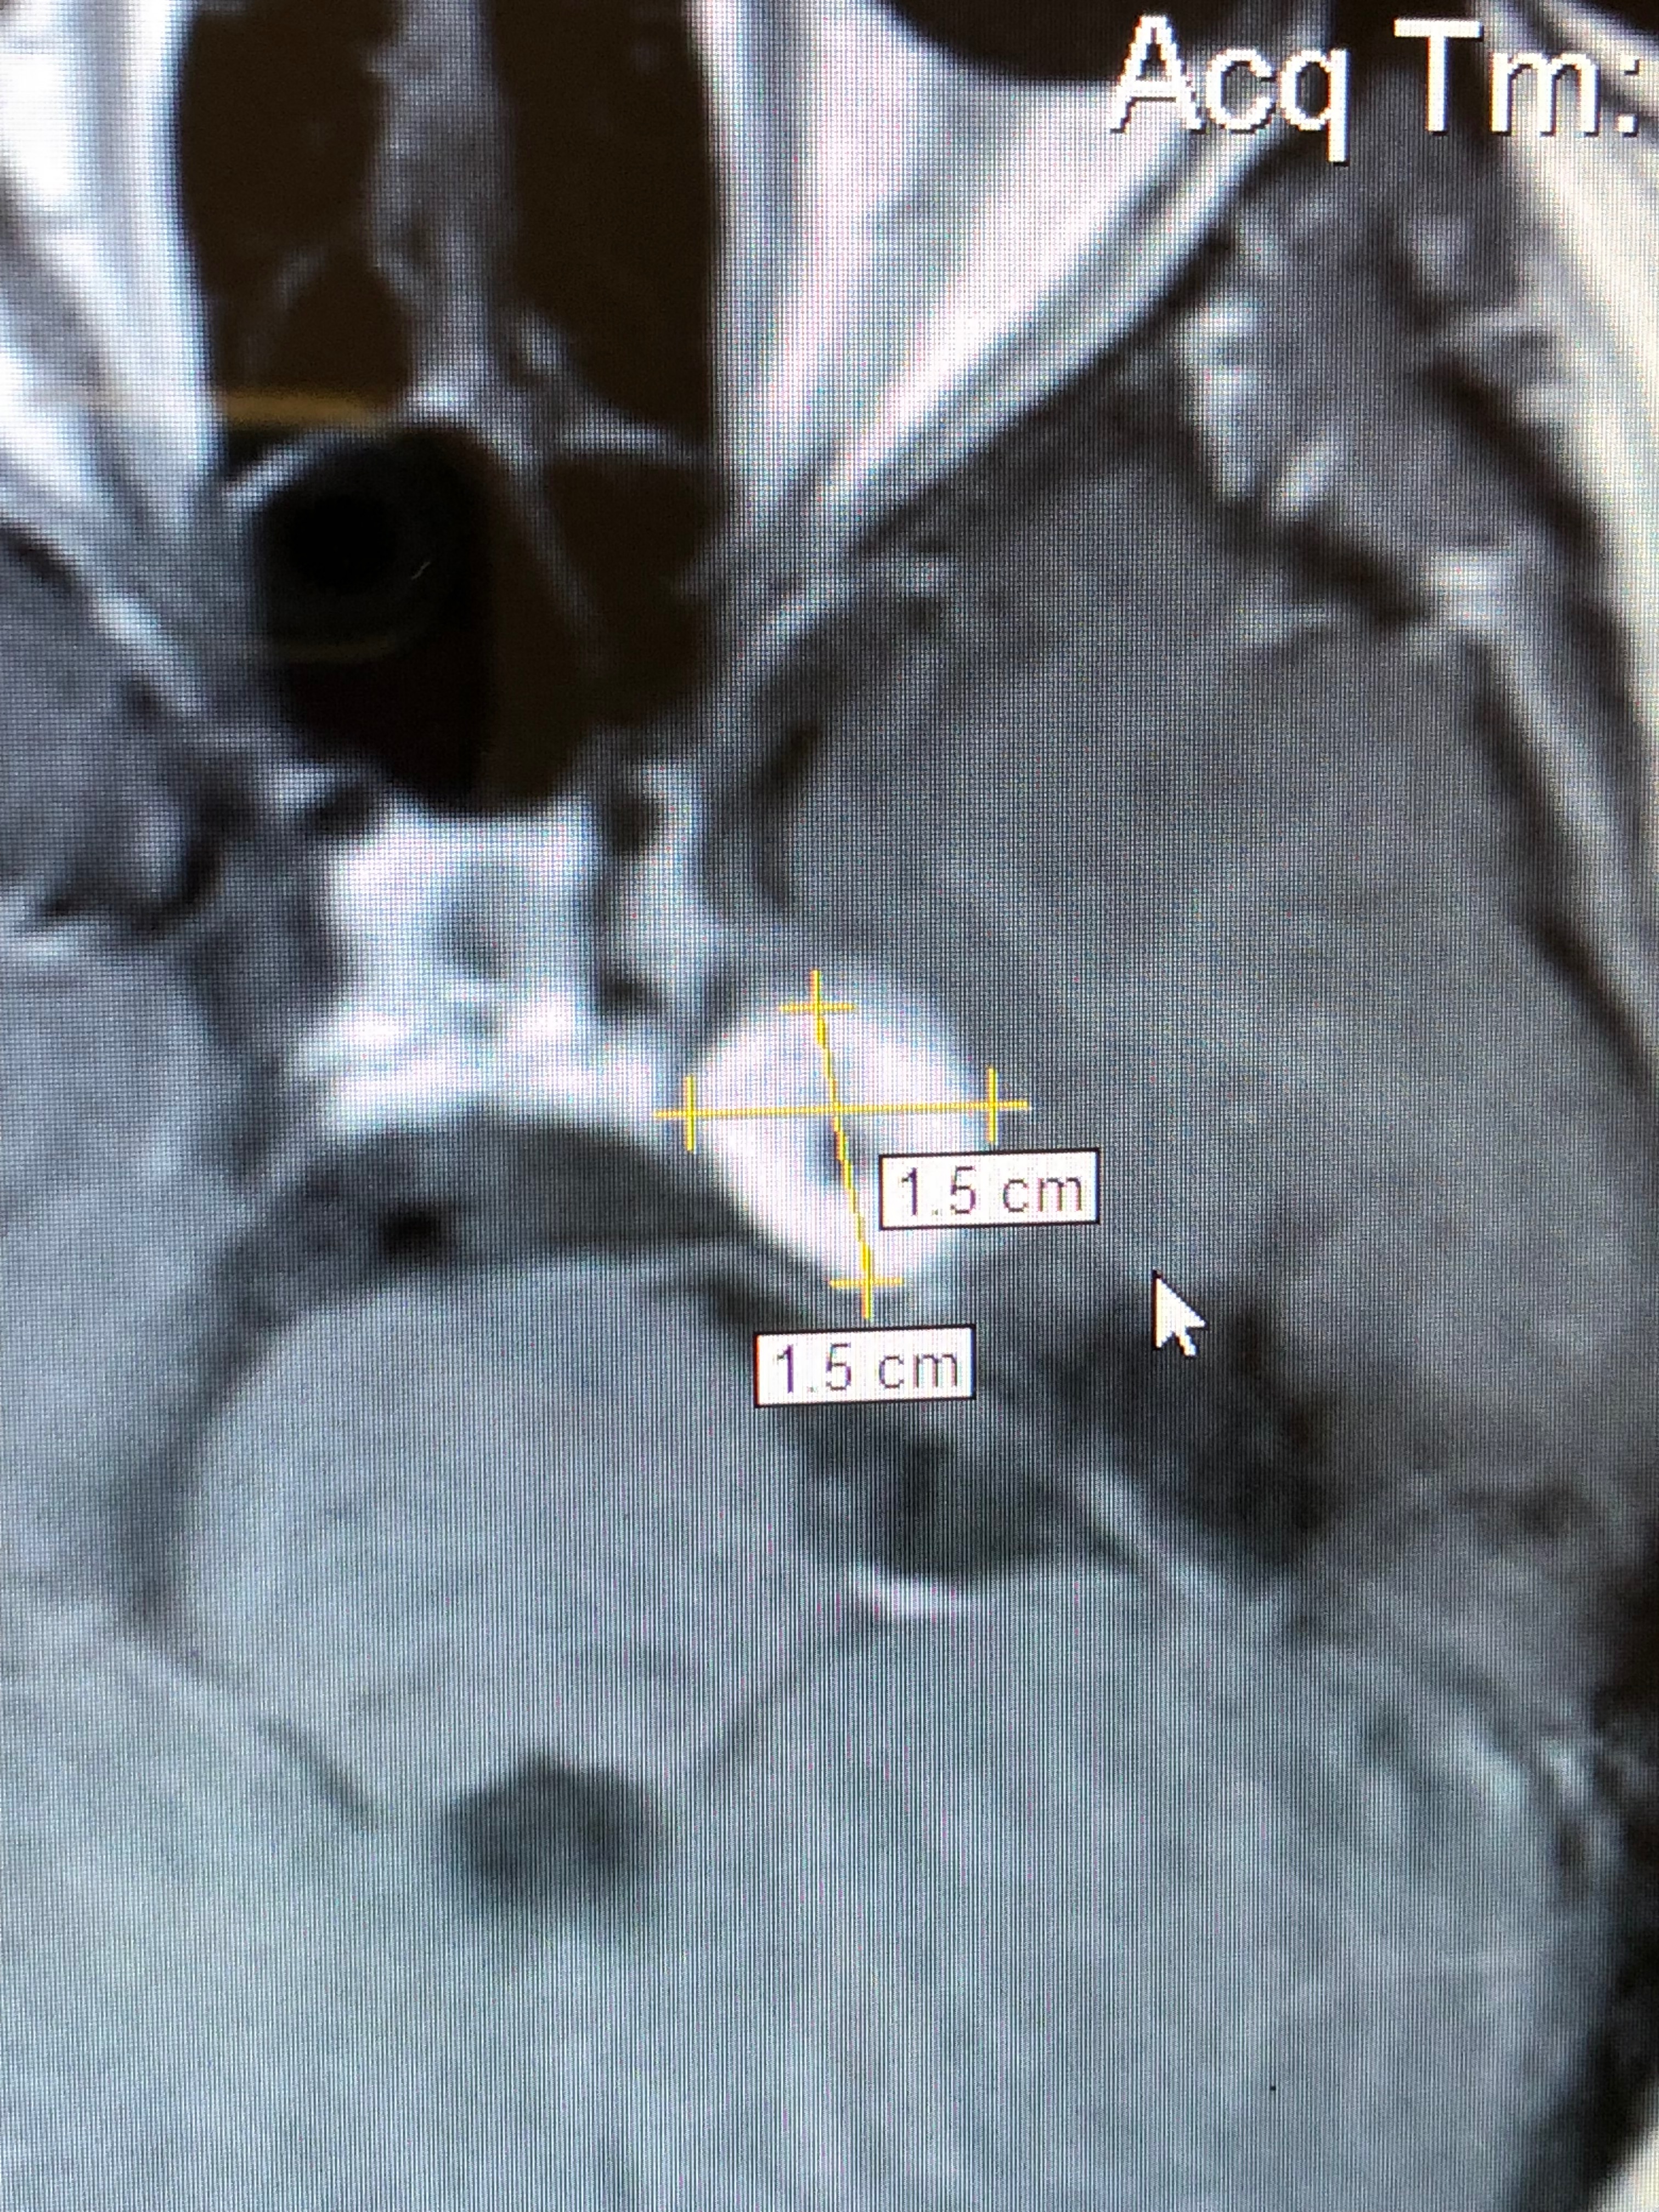

I'm reaching out because I've made the decision to get a service dog to help with my disabilities, which have become more challenging lately. My journey has included recovery from brain tumor removal, an intracranial hemorrhage after surgery, seizures, a blood clotting disorder, adrenal fatigue causing rapid hypotension, Crohn’s Disease, PTSD, and generalized anxiety. Each of these conditions brings its own set of struggles, and together they have made daily life and recovery much more difficult.